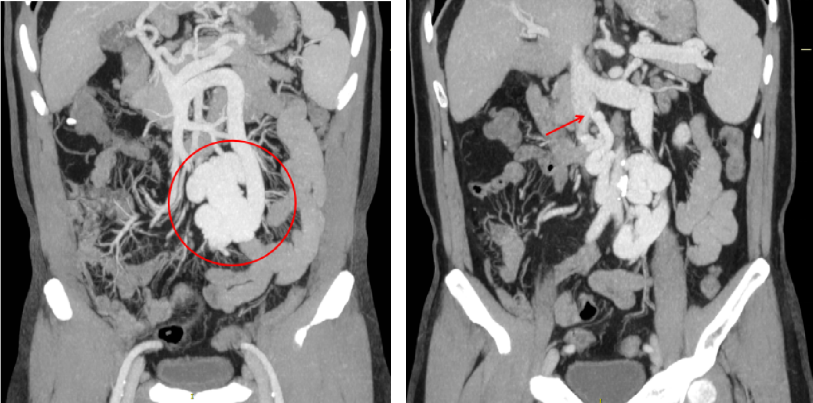

2023-08-10 多排CT全腹部直接增强:肝硬化,脾大,门静脉纤细,食管胃底静脉曲张、异常分流道(肠系膜下静脉-下腔静脉分流,引流端近下腔静脉肾静脉分叉处)

至肠系膜上动脉行间接门静脉造影,未见门静脉显影,可见巨大异常分流道,遂至脾动脉行间接门脉造影可见门静脉异常纤细,肠系膜下静脉见异常分流道形成

异常分流道曲张静脉较前显著萎缩